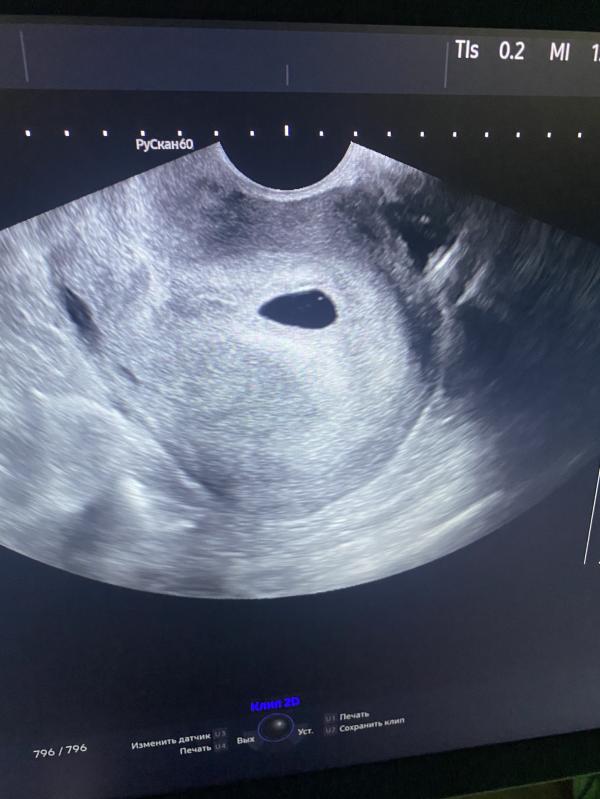

Девочки, кто понимает что то в узи? Сделали мне сегодня, пя в матке, жт есть, но больше врач ничего не сказала. УЗИ сделала быстро и аккуратно, особо не ковырялась, на вопрос может ли это быть замершая беременность, она сказала, что повторное 25 числа узи и там увидим все, пока сказать ничего нельзя, типо беременность, как беременность. Смущает, что эмбрион она не увидила, хотя хгч 10000 уже должно быть. Точно конечно не знаю, но сдавала я 1 числа было 625 и 3 числа было 1363, то есть если через день умножать на 2, то примерно 10тыс получается. Нормально ли это, что до сих пор не видно пя? У кого так было? И может мне еще хгч сдать для успокоения, что все хорошо?

Вы, наверное, ошиблись в посте: плодное яйцо у Вас в полости матки, а эмбрион не визуализируется.

На ХГЧ нет смысла опираться. Мой на сроке 5.2 был больше 10 000, эмбрион не визуализировали, но плодное яйцо было в полости матки. Через неделю сделала контрольное УЗИ. Здесь уже и эмбрион, и сердцебиение.

В 5 недель было только ПЯ и ЖМ, эмбрион увидели в начале 6 недели.

В 5 недель так же только плодное яйцо и жт. Жду 7 недель. ❤